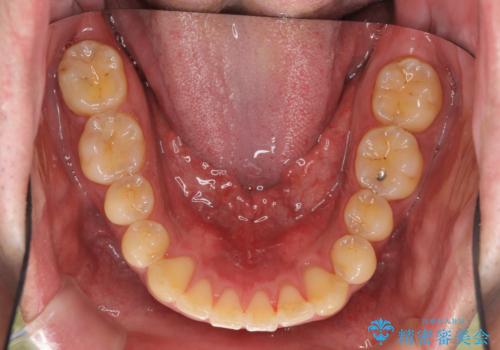

前歯のねじれを 1年かけずに矯正 インビザライン

- インビザライン フル

- 10ヶ月

- 前歯のねじれを主訴に来院。

インビザラインで治療しました。